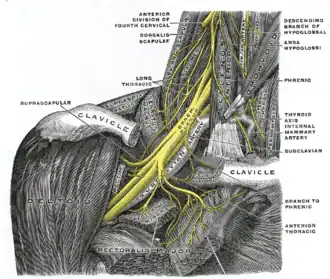

The phrenic nerve emerges from the cervical plexus, with the right brachial plexus shown here. | |

The phrenic nerve is a mixed nerve that originates from the C3–C5 spinal nerves in the neck. The nerve is important for breathing because it provides exclusive motor control of the diaphragm, the primary muscle of respiration. In humans, the right and left phrenic nerves are primarily supplied by the C4 spinal nerve, but there is also a contribution from the C3 and C5 spinal nerves. From its origin in the neck, the nerve travels downward into the chest to pass between the heart and lungs towards the diaphragm.

In addition to motor fibers, the phrenic nerve contains sensory fibers, which receive input from the central tendon of the diaphragm and the mediastinal pleura, as well as some sympathetic nerve fibers. Although the nerve receives contributions from nerve roots of the cervical plexus and the brachial plexus, it is usually considered separate from either plexus.

The phrenic nerve originates in the phrenic motor nucleus in the ventral horn of the cervical spinal cord. It descends obliquely with the internal jugular vein across the anterior scalene, deep to the prevertebral layer of deep cervical fascia and the transverse cervical and suprascapular arteries. On the left, the phrenic nerve crosses anterior to the first part of the subclavian artery. On the right, it lies on the anterior scalene muscle and crosses anterior to the 2nd part of the subclavian artery. On both sides, the phrenic nerve usually runs posterior to the subclavian vein as it enters the thorax where it runs anterior to the root of the lung and between the fibrous pericardium and mediastinal parietal pleura.[2]

The phrenic nerve can be marked by a line connecting these two points:

- 1st point can be labelled 3.5 cm at the level of the thyroid cartilage from the midsagittal plane.

- 2nd point is at the medial end of the clavicle.